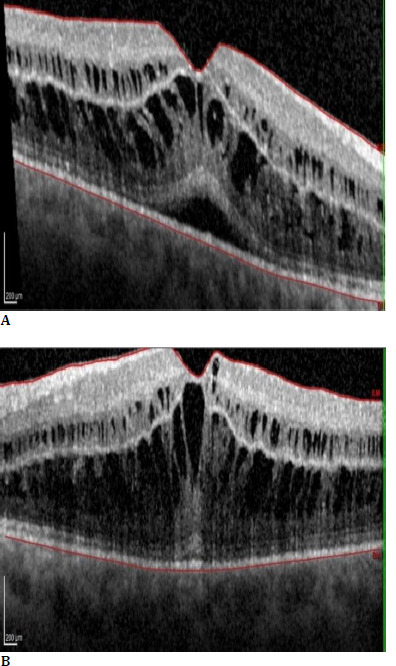

Case presentation: A 69-year-old woman developed a drop in visual acuity that was painless, bilateral, and accompanied by wavy lines. This occurred six months after starting Paclitaxel chemotherapy for metastatic breast cancer. The diagnosis of cystoid macular oedema caused by Paclitaxel was made. The visual acuity significantly improved after Paclitaxel was discontinued, and the symptoms subsided.

Discussion: Paclitaxel is a chemotherapy drug used to treat various types of cancers and has been associated with cystoid macular oedema (CMO) in rare cases. CMO is thought to result from the disruption of the normal blood-retinal barrier. The specific mechanism remains incompletely understood, and multiple mechanisms have been postulated. In typical CMO, leakage from parafoveal capillaries is demonstrated on fluorescein angiograms in a classic petaloid pattern. However, in Taxane-Drug Induced CMO (TDICMO), there is no evidence of fluorescein leakage on angiography. TDICMO is a rare drug side effect of breast cancer treatment, described just 14 times in the English literature.